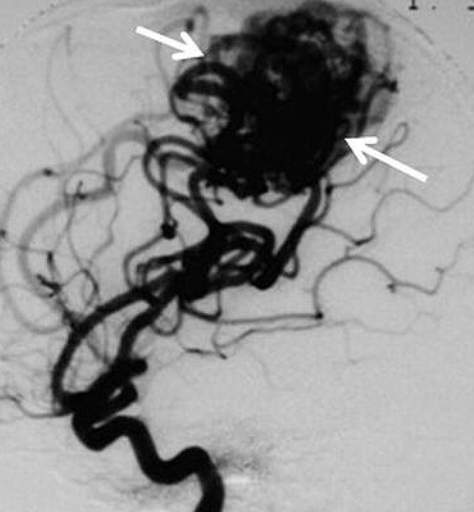

AVM的血管造影

AVM的診斷是通過計算機斷層掃描(CT)、磁共振成像(MRI)和腦血管造影,其中包括x射線(x射線)成像,然后注射造影劑。簡單地說,造影劑被注射到一根導管中,導管插入病人的股動脈,然后通過頸內(nèi)動脈到達大腦。拍攝的影像顯示了AVM的局部位置。這些影像學檢查很重要,因為除了顯示AVM的位置外,它們還可以用來確定AVM的原始大小、治療后的大小變化,以及AVM是否出血或未破裂。通常,AVM 病灶的評估是通過一種名為Spetzler-Martin (SM)分級量表的評分方法進行的,該方法有助于評估手術(shù)死亡風險和嚴重不良反應(SAEs)。SM分級量表考慮到了: